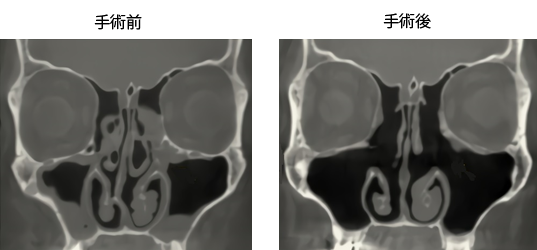

内視鏡下鼻・副鼻腔手術(副鼻腔根治術)

蓄膿症(慢性副鼻腔炎)などに行う手術です。

内服治療しても改善しないとき、改善しても、同じ場所が繰り返し副鼻腔炎になるときに行います。

原因のほとんどが、副鼻腔の排泄路(鼻腔との空気の換気ルート)の閉鎖が改善されないことによるものなので、排泄路を大きく開放し、狭くなる原因(鼻中隔弯曲症やアレルギー性鼻炎)があれば、そちらも一緒に加療します。

手術により、副鼻腔の換気がよくなるため、副鼻腔の炎症も改善しやすく、膿が溜まりにくくなります。

手術する副鼻腔の範囲によって費用が変わります(1型~4型)。手術時間は、手術する副鼻腔の範囲で違い片側15~60分です。

当院では大変解像度のよいCTを導入しています。それにより手術の範囲を決めます。

手術術後には、止血用のタンポンを鼻腔内に詰めて帰宅します。翌日止血用タンポンは抜去しますが、それまでは完全に口呼吸になります。通常、術後1~2週間は、鼻閉、鼻汁、くしゃみが悪化しますが、その後は徐々に症状は改善していきます。術後1か月までは、鼻腔内にカサブタなどがつくため、定期的に外来で通院して副鼻腔処置が必要です。